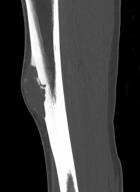

21 year old male with increasing leg pain and enlarging mass for three years

Zoom image: Radiological image Radiological image.